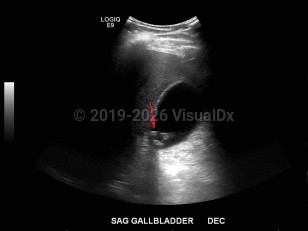

Biliary calculus

Acute cholecystitis